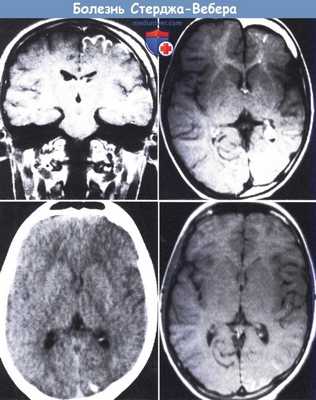

(а) МРТ, FLAIR, аксиальный срез: у женщины 25 лет с «винным пятном» на левой части лица определяются участки повышения сигнала, повторяющие ход извилин левой теменно-затылочной области (симптом «плюща»).

(б) МРТ, постконтрастное Т1 -ВИ, режим подавления сигнала от жира, аксиальный срез: у той же пациентки определяется протяженная пиальная ангиома. Обратите внимание на увеличение размеров ипсилатерального сосудистого сплетения.

(а) МРТ, постконтрастное Т1 -ВИ, режим подавления сигнала от жира, более краниальный аксиальный срез: у той же пациентки определяется контрастирование пиальной ангиомы, заполняющей расширенные борозды. Обратите внимание также на расширенные коллатеральные медуллярные вены, расположенные в белом веществе и осуществляющие венозный отток от пораженной области.

(б) МРТ, постконтрастное Т1-ВИ, режим подавления сигнала от жира, аксиальный срез: у той же пациентки определяется тотальное заполнение интенсивно контрастированной пиальной ангиомой увеличенных извилин конвекситальной поверхности пораженного полушария. (а) МРТ, Т2*SWI, проекция максимальной интенсивности: у той же пациентки определяются расширенные извитые медуллярные вены, расположенные в белом веществе и дренируемые центрально в расширенные субэпендимальные вены.

(б) ЦСА левой внутренней сонной артерии, венозная фаза, боковая проекция: исследование проводилось как часть теста Вада для определения латерализации речи. Определяется недостаточность нормальных кортикальных вен, характеризующихся пролонгированным удержанием контраста вследствие стаза крови в многочисленных расширенных медуллярных венах.